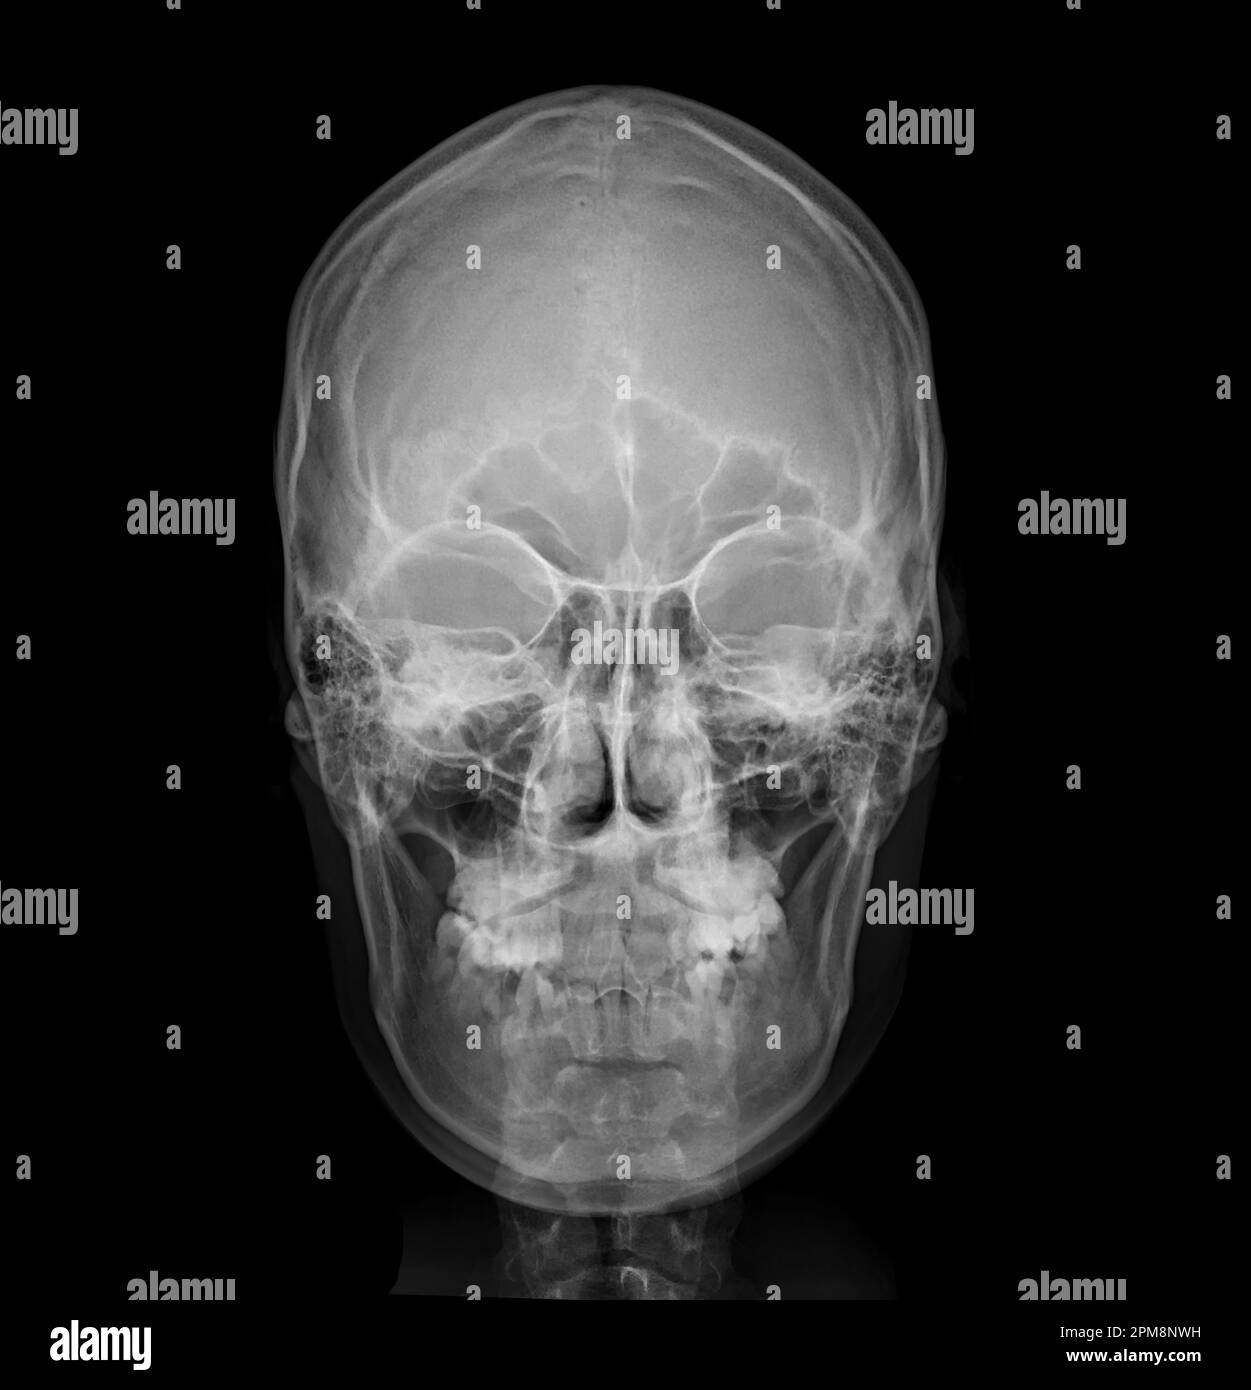

Prepare to be captivated by List, a showcase of real human skull front view black and white imagery powered by ieltschampions.edu.vn. More related visuals are below.

real human skull front view black and white

Posts: real human skull front view black and white